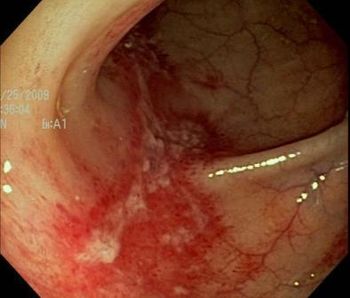

See if the results of this 62-year-old woman's colonoscopy help you identify the source of her abdominal pain.

Eosinophilic esophagitis is often misdiagnosed as gastroesophageal reflux disease but does not respond to acid suppression therapy. Here, a close-to-textbook case.